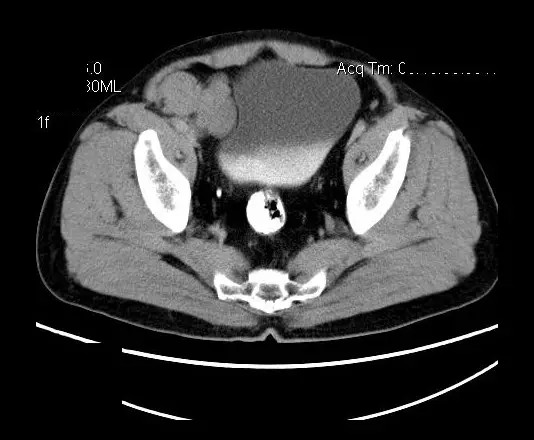

【影像表现】

盆腔右前侧及邻近腹股沟区可见多发大小不等的聚集生长的结节影,病灶呈软组织密度,边缘尚规整,分界尚清,增强扫描可见不均匀强化。膀胱局部受压,盆腔未见明显肿大淋巴结影。

平扫影像表现:Antoni A区较多病灶,在CT上呈等或略高密度影,T1WI等信号、T2WI略高信号,AntoniB区较多病灶,CT多为水样低密度、T1WI低信号、T2WI明显高信号。

增强影像表现:神经鞘膜肿瘤增强后,由于Antoni A区与B区以不同比例混合而强化不一,呈不均匀斑片状,条状强化。Antoni A 区富血供,中等或明显强化,Antoni B区乏血供,强化多不明显。